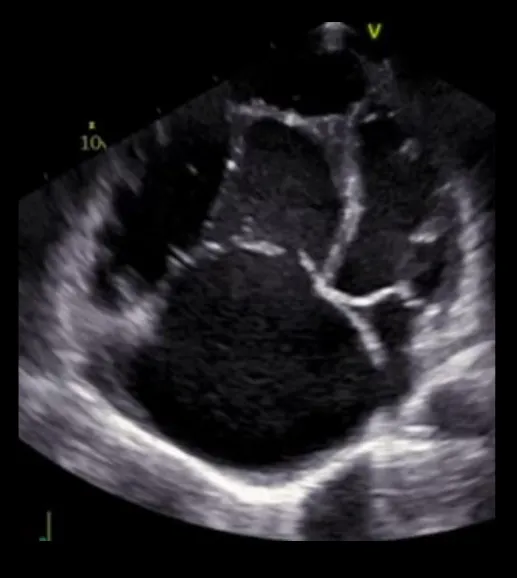

Figure 1

Pathophysiologic Subdivision of Tricuspid Regurgitation. Primary tricuspid regurgitation is caused by abnormalities/damage on the tricuspid valve apparatus (A) (e.g., prolapse of the leaflet or endocarditis). Left heart related tricuspid regurgitation and precapillary pulmonary tricuspid regurgitation (B) are caused by dilation of the right ventricle, papillary muscle displacement and tethering of the tricuspid valve leaflets with malcoaptation. In isolated tricuspid regurgitation (C) the tricuspid annulus is pronouncedly dilated due to dilation of the right atrium in the presence of atrial fibrillation or diastolic dysfunction.

Isolated (idiopathic) tricuspid regurgitation (ITR) is described as a morphologic type of TR in the absence of left-heart sided causes, pulmonary hypertension or primary right ventricular diseases. Hence, it is recognized as a separate entity (other than secondary TR) (9, 20, 30). In the absence of pronounced pulmonary hypertension, the right ventricle shows a not so dominant elongation but rather a dilation of the basal segments (11). Additionally, 3D-Echocardiography with tricuspid valve analysis using 3D-quantifation software revealed that the tricuspid annulus in patients with ITR was pronouncedly more dilated, planar, circular and dysfunctional than in patients with LH-TR with less leaflet tethering and tenting volume (Figure 1C) (11). Patient characteristics are also different to LH-TR. Isolated TR mostly appears in female patients of advanced age with smaller body surface area, lower likelihood of coronary artery disease and higher rate of arterial hypertension and in particular atrial fibrillation (14). The RA shows a higher degree of enlargement. Rotational and helical blood flow within the RA is hence disrupted, particularly in atrial fibrillation, which may contribute to TR progression (10, 31). Utsonomya et al. described a prevalence of 9.2% of isolated tricuspid regurgitation in patients diagnosed with at least moderate TR (11). Topilsky et al. could show that 8.1% of significant TRs diagnosed in American community residents were of isolated origin (14). Interestingly, diastolic dysfunction (heart failure with preserved ejection fraction; HFpEF) seems to be another key mechanism in isolated TR in patients without atrial fibrillation (20). Interestingly, Mascherbauer et al. found that 51% of routinely followed HFpEF patients had at least moderate secondary TR. Patients with TR had a higher pulmonary vascular resistance, reduced pulmonary compliance, and elevated left ventricular filling pressure compared to those presenting without TR (20). Therefore, tricuspid regurgitation – once diagnosed – should entail further assessment of the left ventricle, in particular with regard to diastolic dysfunction (20) and vice versa patients with diagnosed HFpEF should be monitored for worsening RV function and TR.